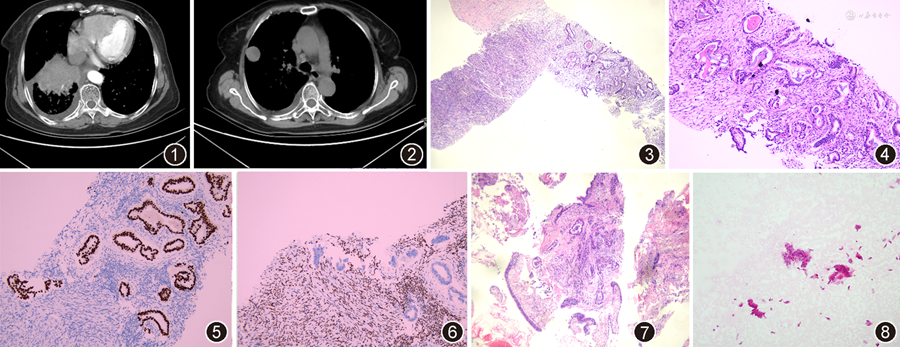

患者女,64岁。2021年11月以“肺部占位性病变”就诊于兰州大学第二医院,行胸部增强CT示:双肺透亮度欠均匀,支气管血管束紊乱,右肺下叶近肺门处可见直径约7 cm形态不规则的软组织占位性病变,呈浅分叶状,相邻胸膜牵拉,病灶呈中度强化,其内可见细小血管穿行,右肺下叶支气管狭窄闭塞,双肺多发结节样密度增高影,右肺上叶胸膜下可见一直径约3.1 cm类圆形结节影,边界光整,与相邻胸膜紧密相连,呈持续渐进性强化(图1,2)。肿瘤标志物检测:神经元特异性烯醇化酶(NSE):18.40 μg/L,细胞角蛋白(CK)19片段CY211:6.25 μg/L。胸腹部增强CT扫描示:肝脏、胆囊、胰腺、双肾、双侧肾上腺、膀胱、子宫等形态大小及密度未见异常,腹膜后淋巴结未见肿大。行支气管活检及肺穿刺术。

病理检查:送检组织有3类。(1)右肺上叶灰白色穿刺组织2条,长0.5、1.0 cm,直径均为0.05 cm。(2)支气管镜取材:灰白色组织数粒,直径约0.5 cm。(3)另送纤维支气管镜刷片组织。镜下观察:(1)右肺上叶胸膜下穿刺组织中可以见到2种成分:背景为梭形细胞肿瘤,瘤细胞排列成束条状、席纹状或无结构生长模式,部分区域细胞密集,部分区域细胞稀疏,可见胶原沉积,核分裂象罕见;在梭形肿瘤区域内可见多灶异形腺体浸润,细胞核增大、深染(图3,4)。免疫组织化学染色显示梭形瘤细胞阳性表达STAT6(图5)、CD34,Ki-67阳性指数2%;异形腺上皮阳性表达细胞角蛋白(CK)7、甲状腺转录因子1(TTF1,图6)、Napsin A、上皮细胞膜抗原(EMA),Ki-67阳性指数30%。分子检测:表皮生长因子受体(EGFR)基因第18、20、21号外显子野生型,第19号外显子缺失突变;间变性淋巴瘤激酶(ALK)融合基因检测:未见融合。(2)支气管取材镜检:(右下基底支)送检组织中可见异型腺体,呈不典型腺管样、核大、深染(图7),免疫组织化学染色见腺体细胞阳性表达CK7、广谱细胞角蛋白(CKpan)、TTF1、Napsin A,Ki-67阳性指数30%。(3)纤维支气管镜刷片:查见异型细胞团,核中度异形,排列紊乱(图8)。

病理诊断:(1)肺腺癌;(2)肺腺癌肿瘤间转移至胸膜孤立性纤维性肿瘤;(3)纤维支气管镜刷片内查见癌细胞。